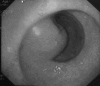

Figure 2

Figure 2. Endoscopic view showing a submucosal lesion located at the gastric antrum, causing partial obstruction of the pylorus, with intact mucosal.